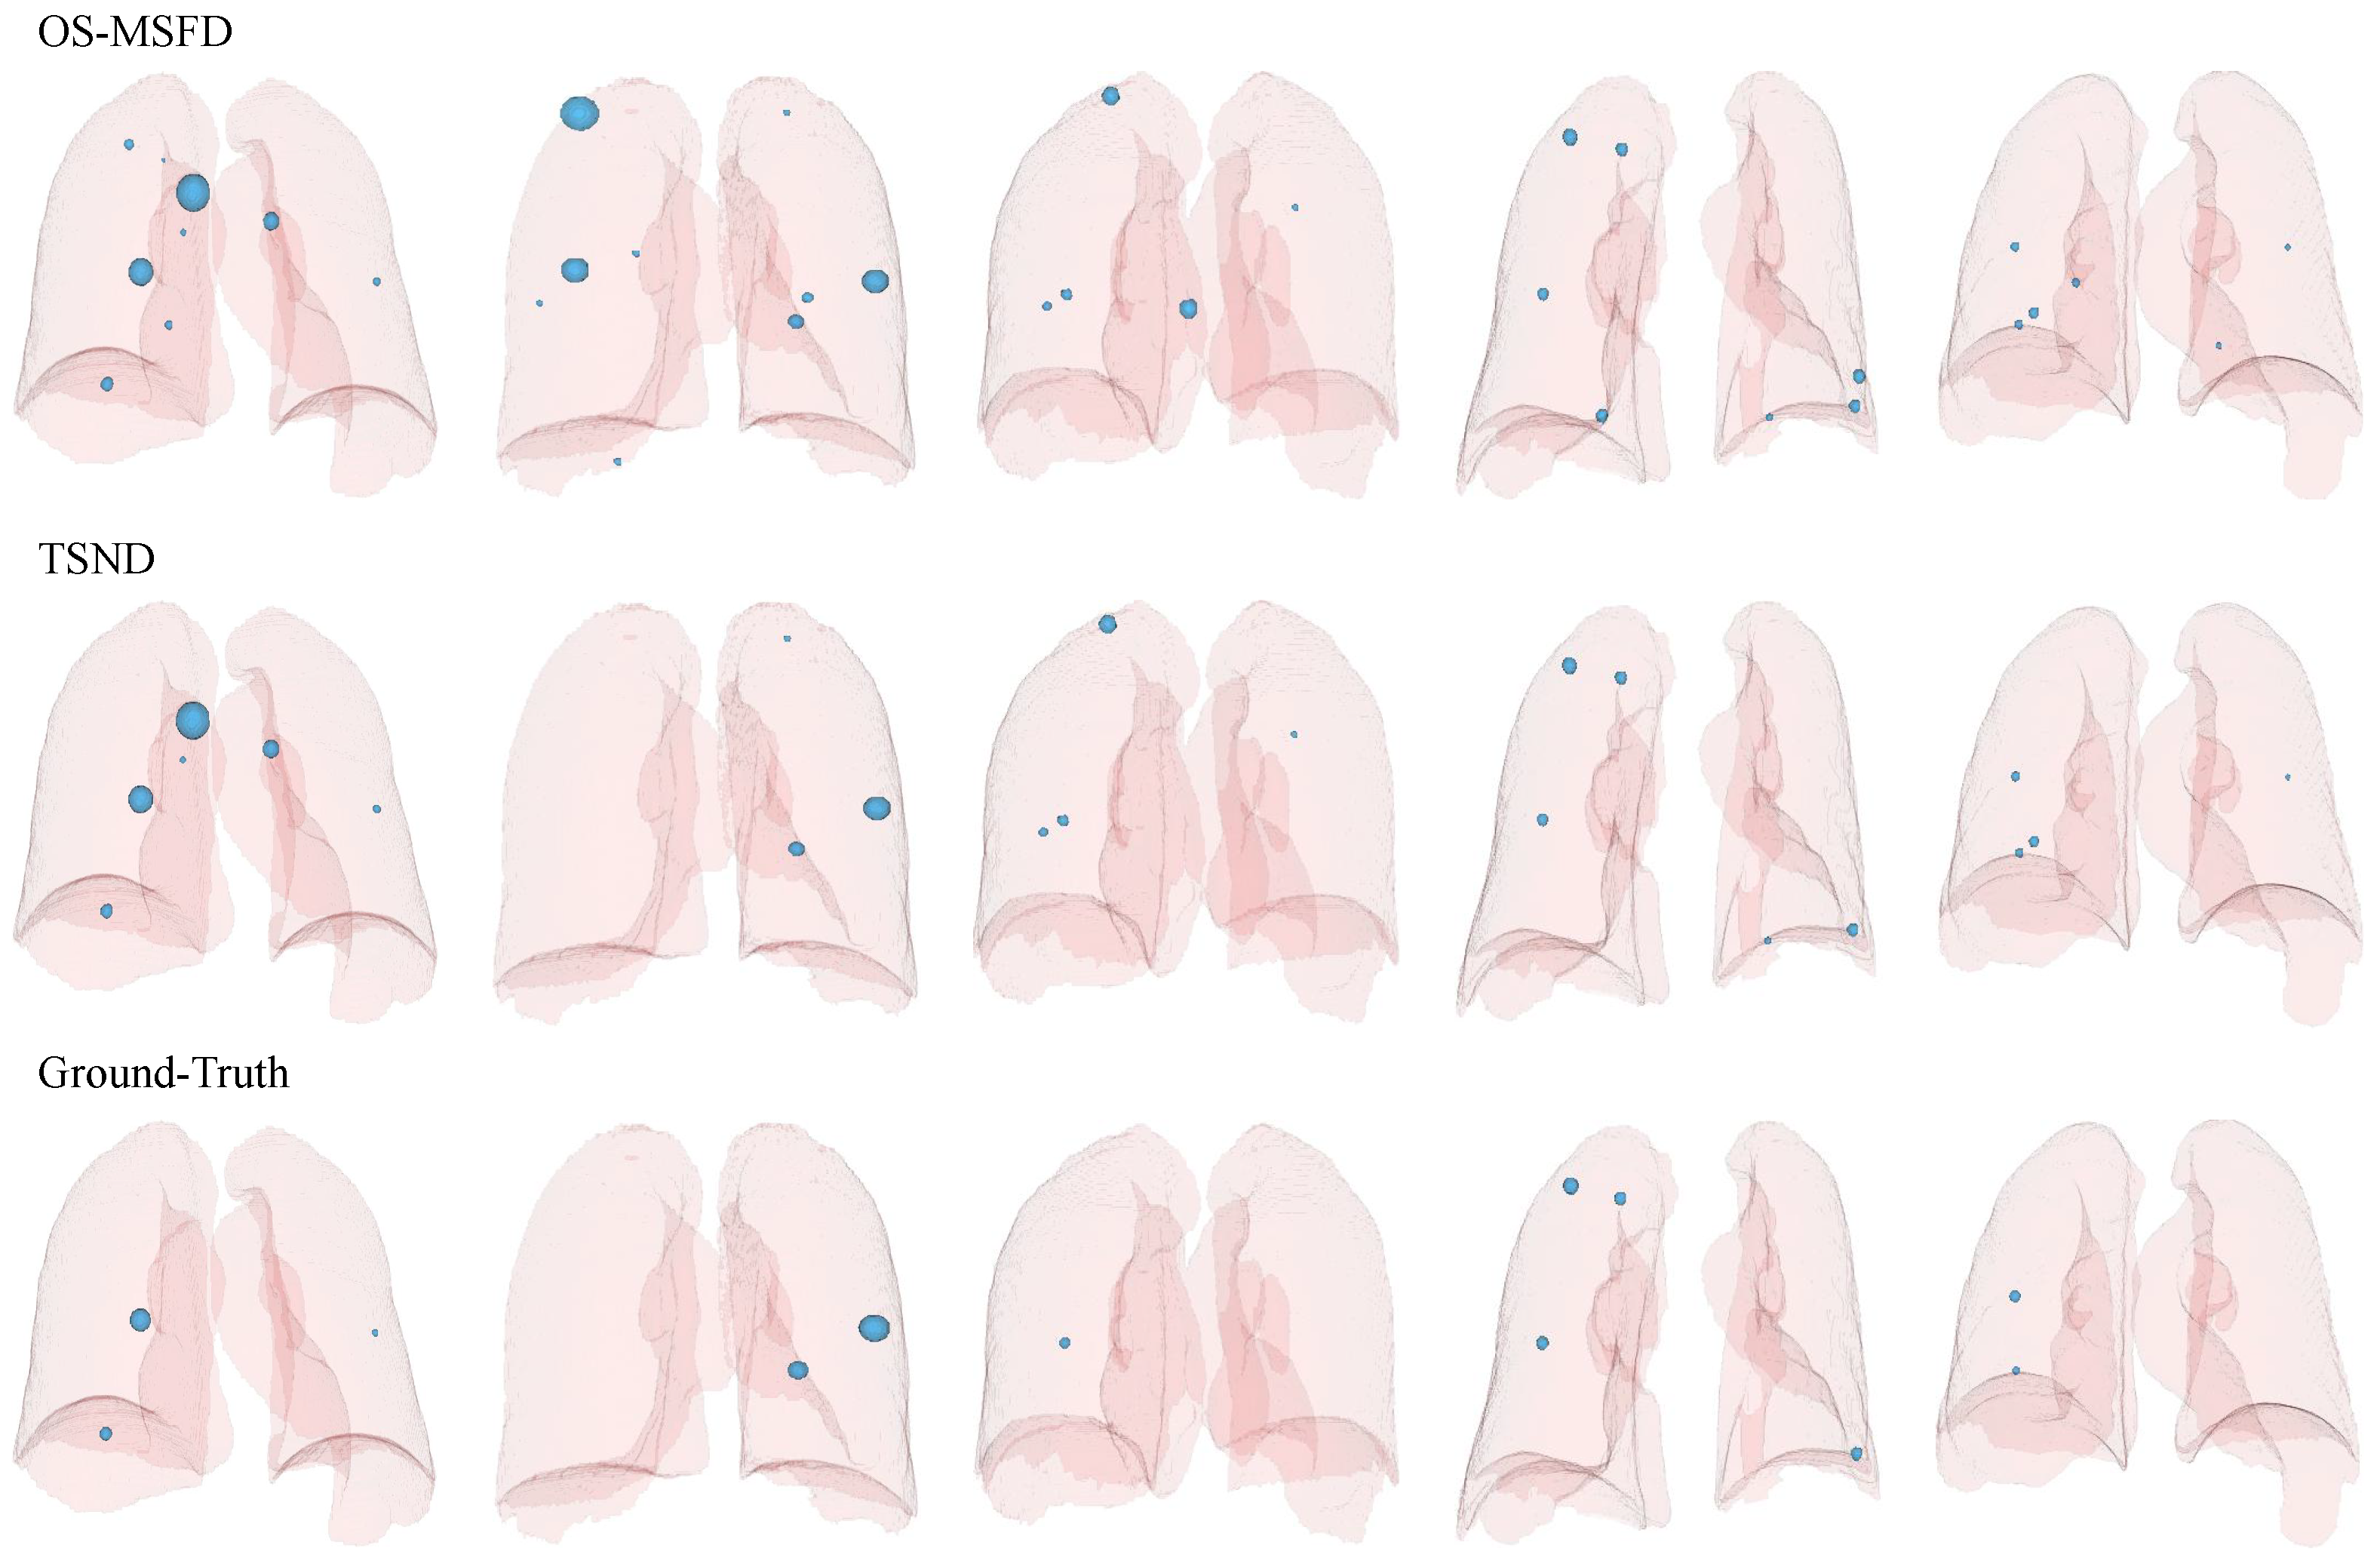

4.4. Visualization